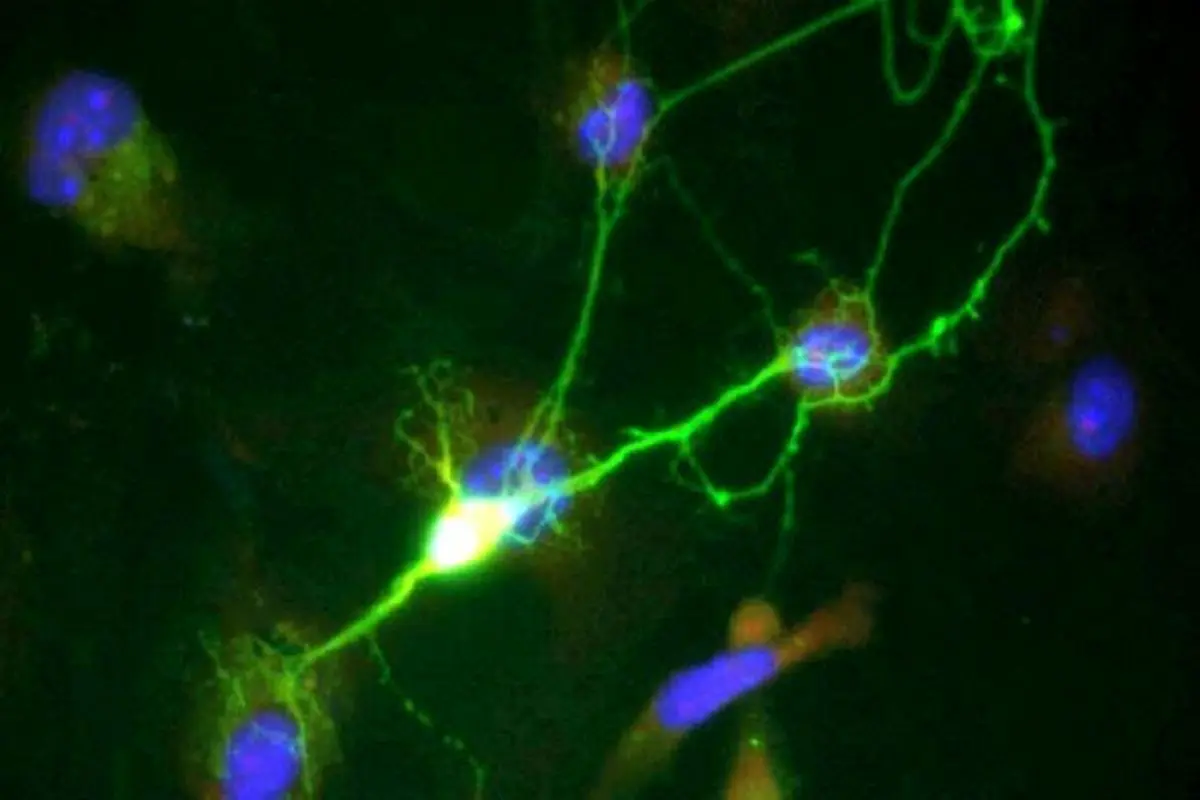

دانشمندان دانشگاه کشف کرده‌اند که اگرچه تغییرات نورون‌های مغزی، از جمله از دست رفتن سلول‌ها، ممکن است از اوایل زندگی آغاز شود، اما دارویی که مدت‌هاست برای بیماری‌های دیگر تایید شده، می‌تواند برای کند کردن این آسیب دوباره مورد استفاده قرار گیرد؛ موضوعی که امید تازه‌ای را برای مبتلایان به بیماری آلزایمر و دیگر اختلالات شناختی ایجاد می‌کند.

به نقل از مدیکال اکسپرس، مطالعه جدید در یک بررسی مقطعی روی افراد در همه سنین نشان داد که پروتئینی به نام UCH-L1 که از نورون‌های در حال مرگ مغز وارد خون می‌شود و پروتئین دیگری به نام NfL که از نورون‌های آسیب‌دیده آزاد می‌شود، در اوایل زندگی در غلظت‌های پایینی در خون حضور دارند، اما سطح آن‌ها هر سال تا سن ۸۵ سالگی به‌طور نمایی افزایش می‌یابد.

تغییرات اولیه این نشانگر زیستی در اوایل زندگی احتمالا بازتابی از فرایند طبیعی پیری است، اما در مراحل بعدی زندگی، افزایش سطح UCH-L1  با پیامدهای دیگر مرتبط است. این کشف می‌تواند به آزمایش‌های زودهنگام‌تر و درمان‌های جدید برای آلزایمر و احتمالا افت شناختی ناشی از پیری طبیعی منجر شود.